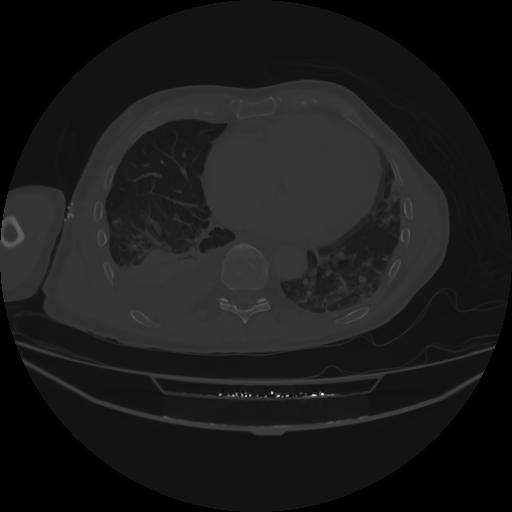

5 CUERPO,CE,Vol,1.0,CUERPO,,